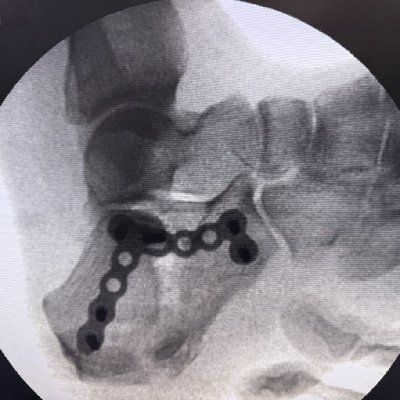

Minimally Invasive Surgery (MIS) :

- Ankle Arthroscopy

- Endoscopic Calcaneoplasty

- Posterior Arthroscopy